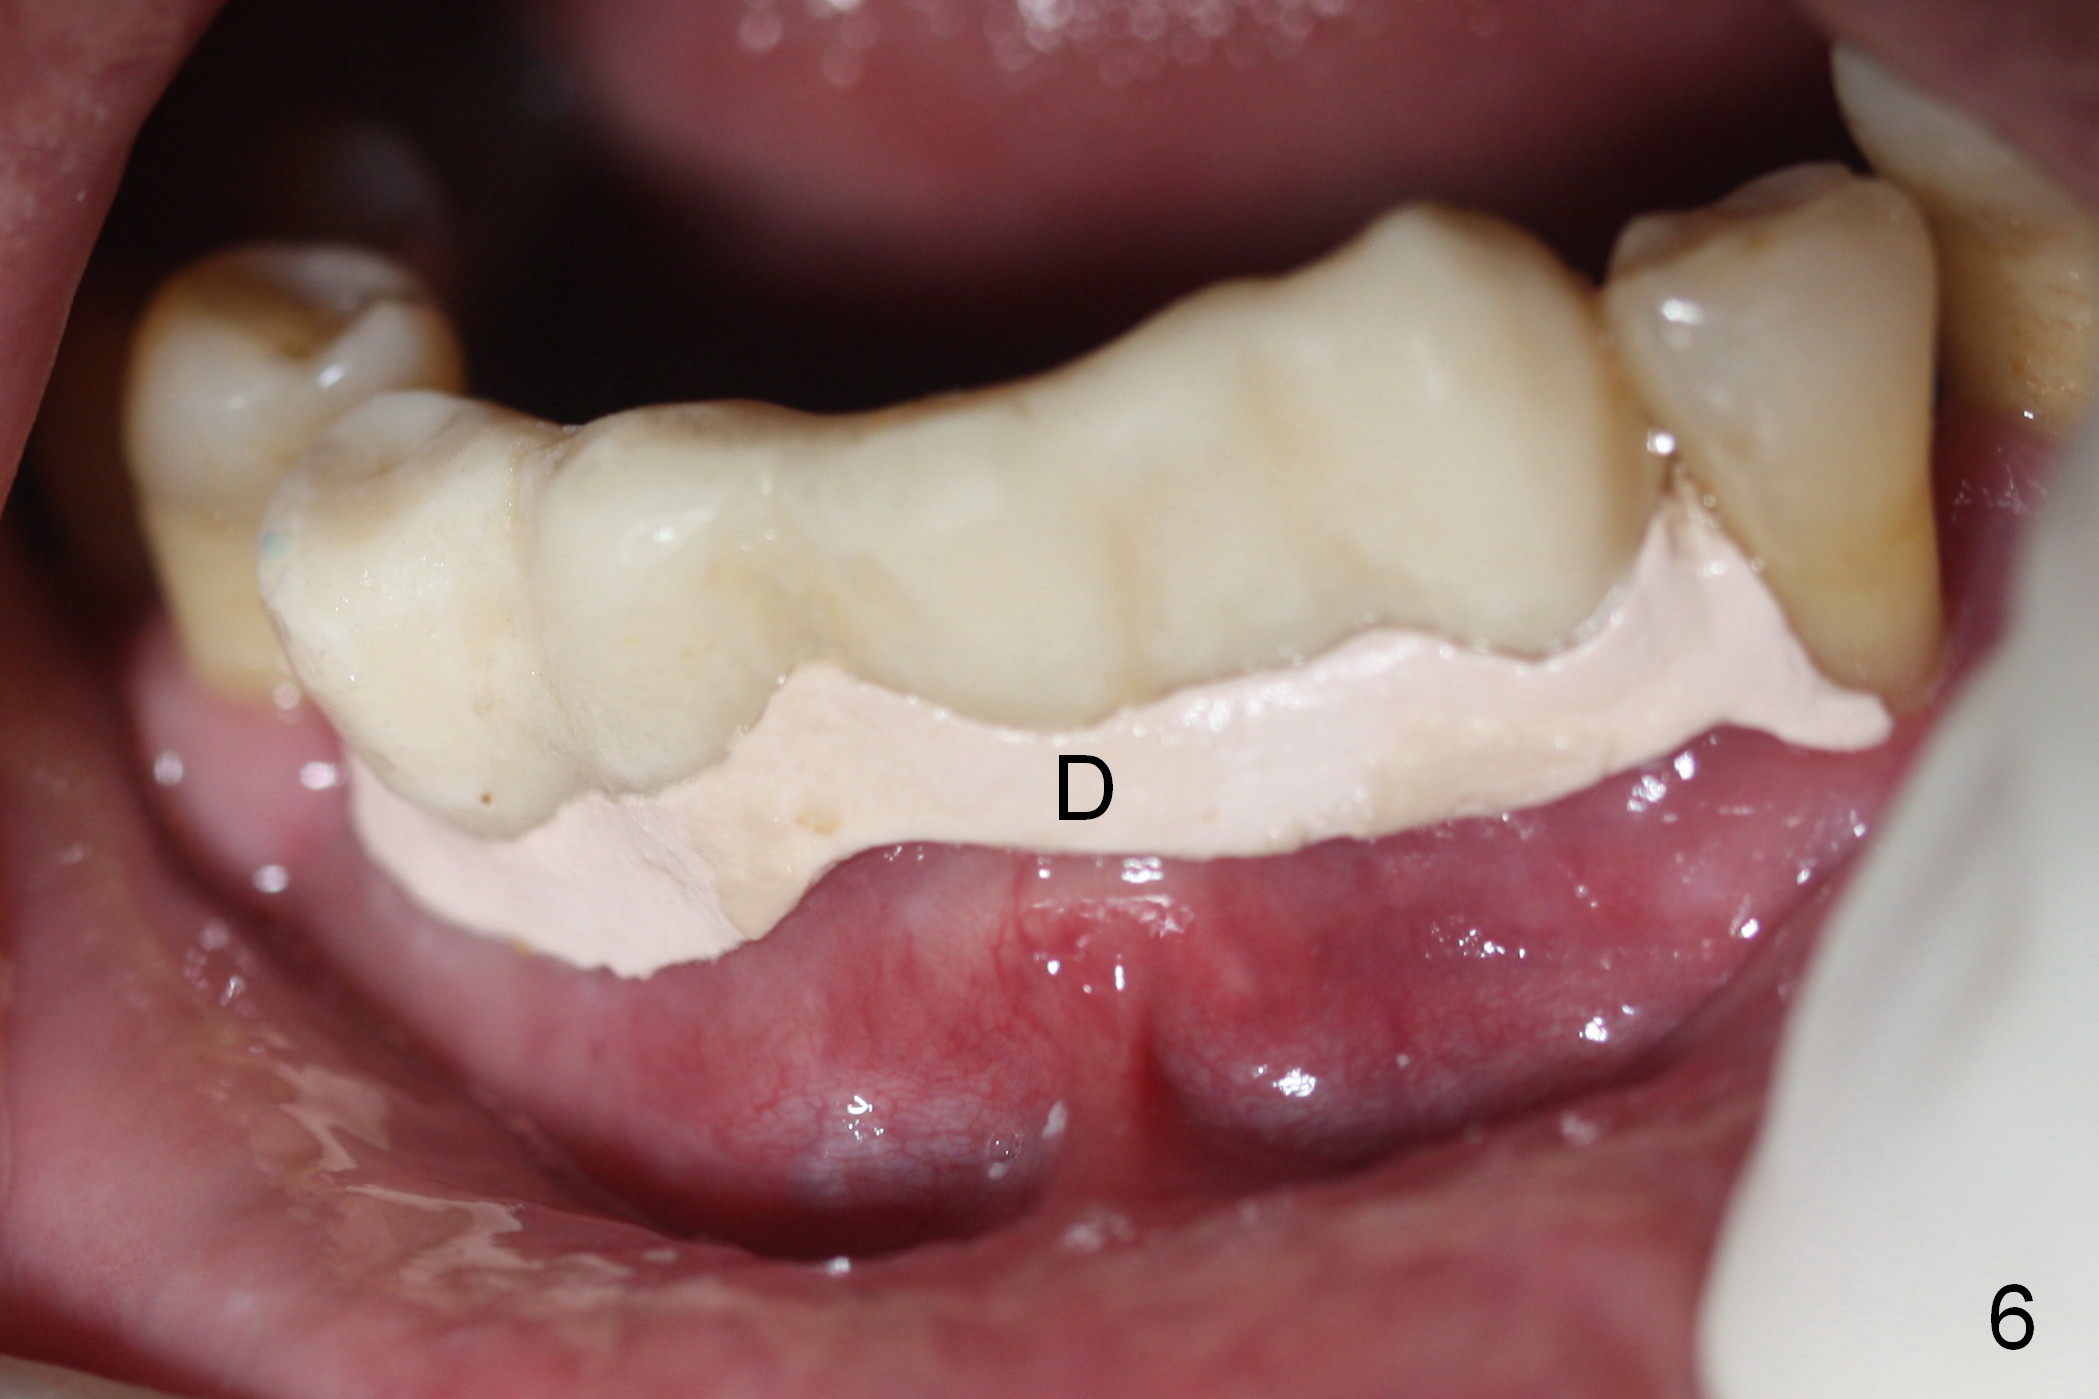

As expected, the bone density in the mandibular anterior region is found to be high during initial osteotomy (Fig.1-3). Five implants are placed at the sites between #22 and 28 (Fig.4,5): 3x14(2) mm 1-piece (bone-level) implants in the incisor region; 4.5x17 mm 2-piece (tissue-level) ones in the canine/premolar area. All of the implants are placed as lingual as possible. Bone graft is placed (*). Red dashed line: the superior border of the Inferior Alveolar Canal. Immediate splinted provisional bridge is fabricated. One week postop, periodontal dressing remains attached to the provisional and the gingiva.